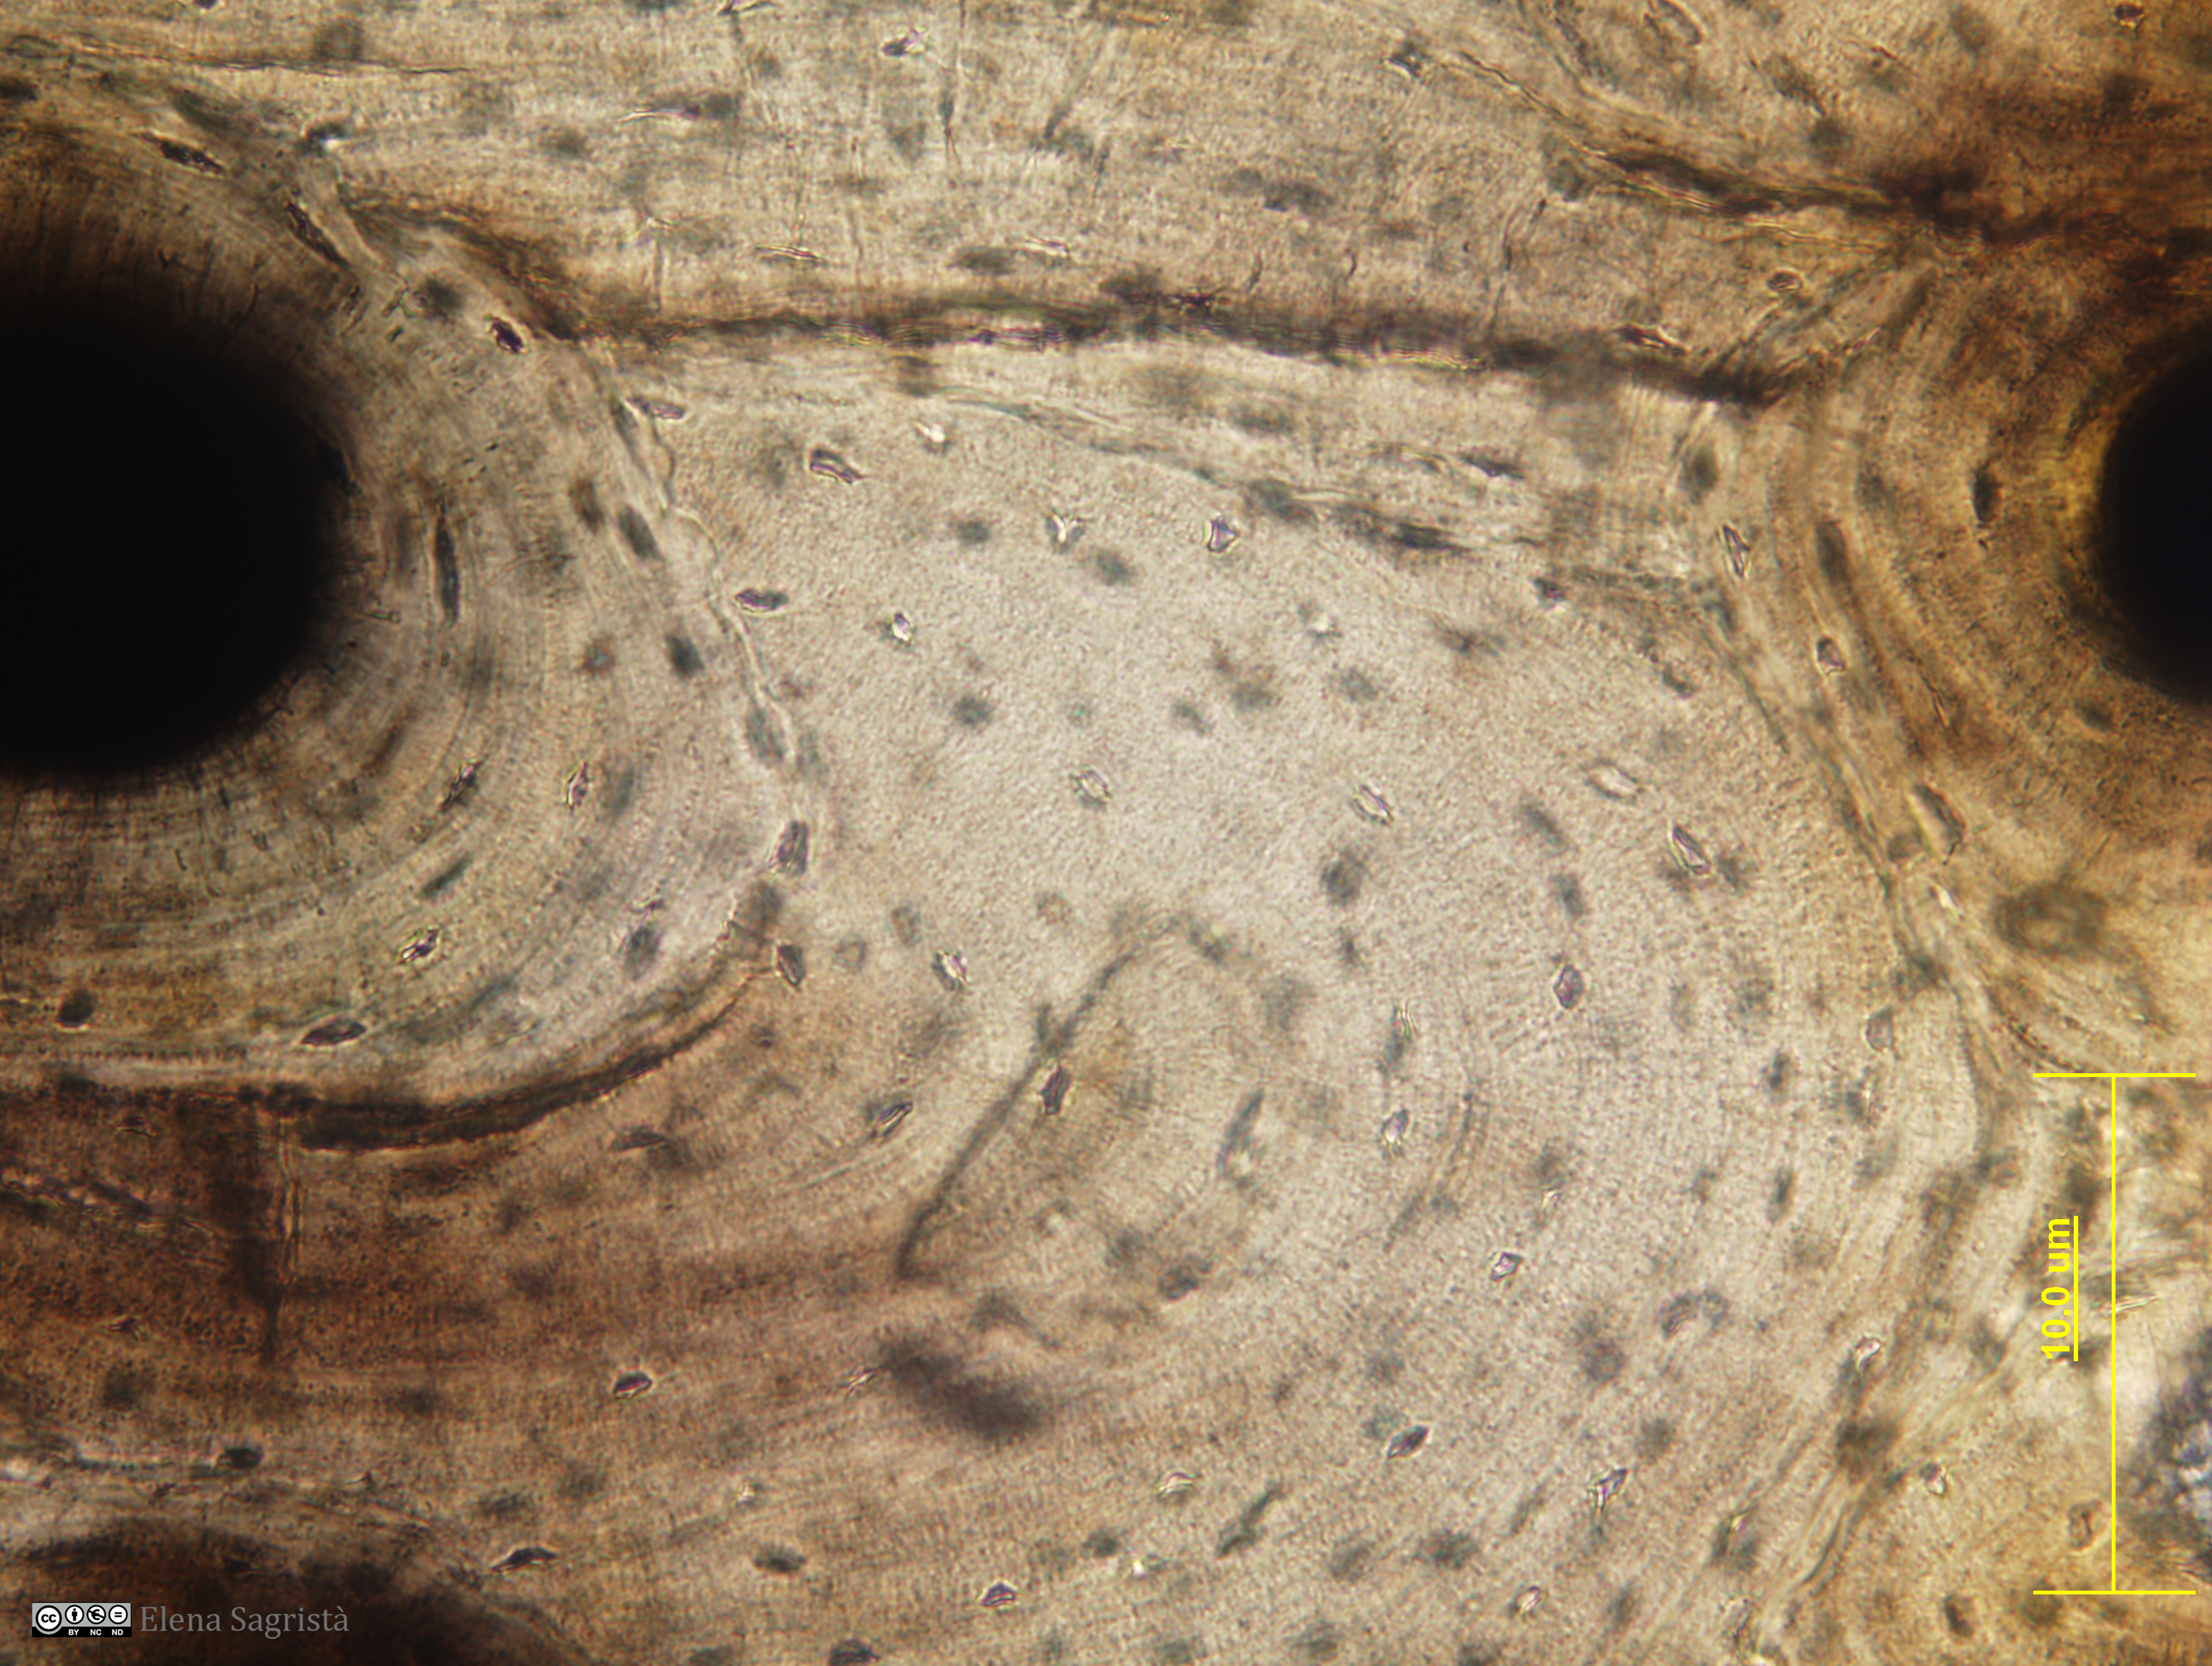

Histologia imatges: 05 Teixit ossi

Imatges de preparacions histològiques de Teixit ossi. Microscopia òptica.